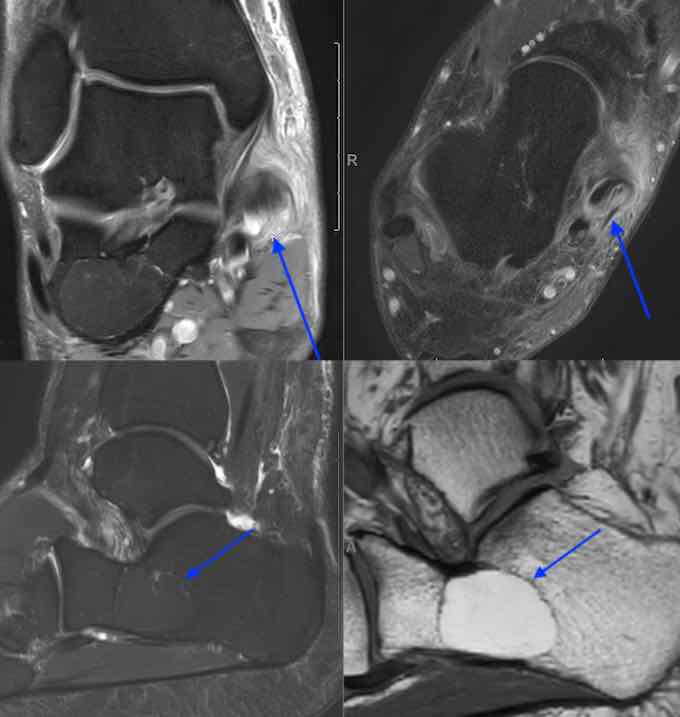

IMAGE DU MOIS - CASE OF THE

MONTH

Brain sag. FLAIR, cor. T1 Gd,

axial T1 Gd & T2: cerebellum hemangioblastoma.